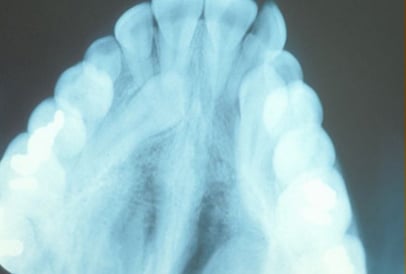

Normally, the maxillary cuspid teeth are the last of the “front” teeth to erupt into place. They usually come into place around age 13 and cause any space left between the upper front teeth to close tighter together. If a cuspid tooth gets impacted, every effort is made to get it to erupt into its proper position. The techniques involved to aid eruption can be applied to any impacted tooth in the upper or lower jaw, but most commonly they are applied to the maxillary cuspid (upper eye) teeth. Sixty percent of these impacted eyeteeth are located on the palatal (roof of the mouth) side of the dental arch. The remaining impacted eye teeth are found in the middle of the supporting bone, but are stuck in an elevated position above the roots of the adjacent teeth, or are out to the facial side of the dental arch.

The older the patient the more likely an impacted eyetooth will not erupt by natural forces alone, even if the space is available for the tooth to fit in the dental arch. A panoramic x-ray, along with a dental examination, will help determine whether all the adult teeth are present or if some adult teeth are missing.